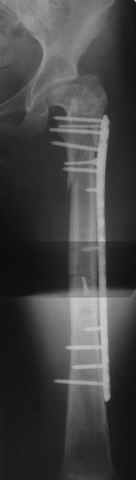

Уважаемые коллеги, приношу извенения за молчание. Готовили материал и боялись писать раньше времени. Все хотели убедиться в том, что после операции все будет спокойно. Спасибо за отклики и советы. К сожалению, гамма-гвоздя, штифтов с возможностью установки более 2-х блокирующих винтов у нас нет. Зато нашли достаточно длинную пластину с угловой стабильностью. После проведения предоперационной подготовки и планирования выполнили остеосинтез. В условиях рентгеноперационной, после репозиции дистрактором из одного разреза 5см в проксимальном отделе подкожно установили пластину. Пришлось выполнить дополнительный разрез до5см в проекции перелома диафиза в средней трети, из которого удалось репонировать перелом и выполнить фиксацию стягивающим винтом. Затем все завершилось наложением пластины с угловой стабильностью. Пластина оказалась достаточно длинной, что позволило перекрыть все переломы с фиксацией каждого отломка минимум 5-ю винтами. Синтез достаточно стабилен. Пациентка активизирована на 3-и сутки(снимки прилагаются). В настоящий момент пациентка выписана на амбулаторное лечение. Еще раз, огромное спасибо всем за помощь в выборе тактики и просто совете. С уважением Украинский Е.

Прошу прощения, со снимками глюк произошел. Высылаю. С уважением Евгений У.

Получилось очень симпатично, мои поздравления. А можно фото конечности без наклеек посмотреть?

И межфрагментарный винт на диафизе - так ли он нужен при выбранном варианте остеосинтеза с относительной стабильностью?